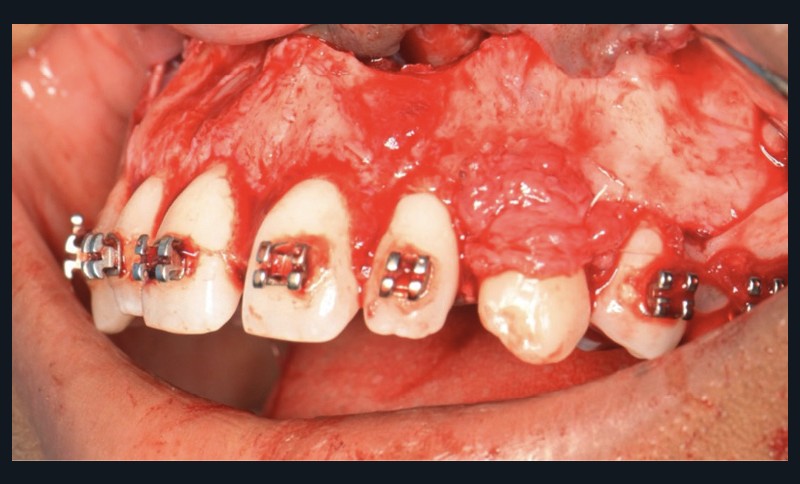

Une fois l’espace nécessaire obtenu, des cales molaires sont réalisées pour limiter les interférences occlusales avec la 23. La 63 et l’odontome sont extraits (fig. 4). Un lambeau est levé et la réplique 3D de la 23 est essayée dans l’alvéole, qui est adaptée en fonction (fig. 5). La 23 est prélevée de façon atraumatique (fig. 6) et auto-transplantée (fig. 7). Après suture du lambeau (fig. 8), une contention par arc acier 0,019×0,025’’ avec un CVI entre la dent et l’arc orthodontique est réalisée (fig. 9). Trois ou quatre semaines après l’auto-transplantation (fig. 10), le traitement endodontique est effectué (fig. 11). Un bracket orthodontique pourra être collé de façon passive, et la dent prise en charge avec un arc Niti 0,017 x 0,025’’ (fig. 12).